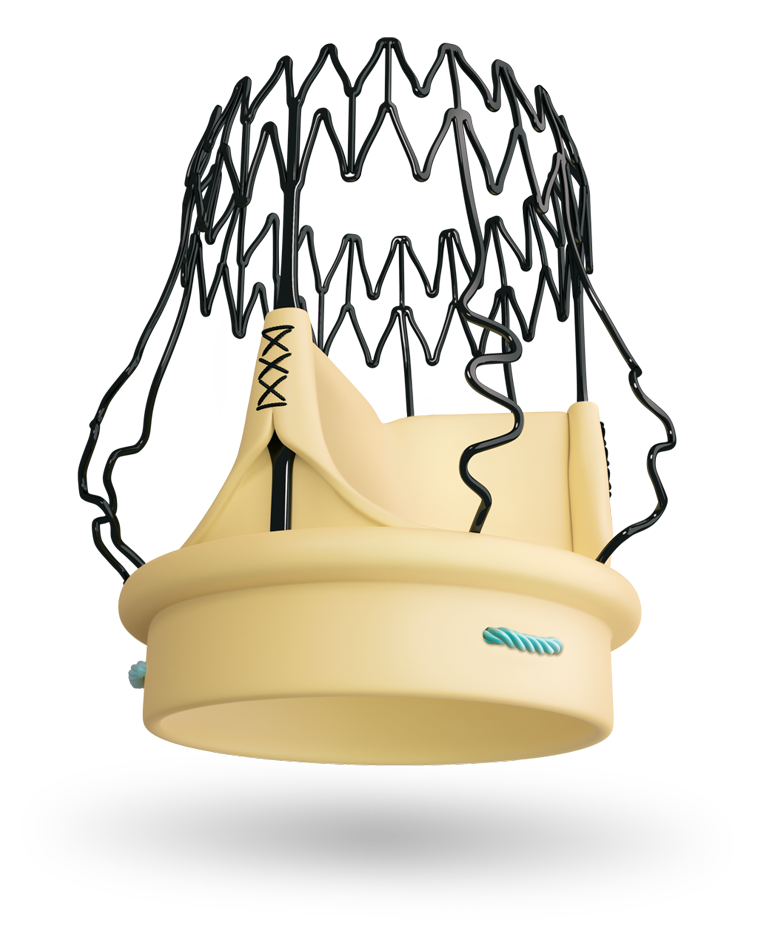

Perceval Plus is based on the trusted Perceval Platform

The Perceval Platform is based on a sutureless and collapsible design that simplifies the surgical implantation, reducing the impact of surgery and facilitating faster recovery.1,2

Unique design: unique benefits

Designed for durability

Superlastic stent

- Self-expands in place (no need to knot the sutures), ensuring optimal valve sealing.2

- Reduces the stress transferred to the leaflets.4

- CarbofilmTM coated to reduce inflammatory reaction and favor a gentle endothelialization.5,6,7

Double sheet design

An outer sheet acts as a cushion that minimizes stress transferred to the leaflets.

Fully atraumatic collapsing

The collapsing procedure does not affect the leaflets preventing any possible damage to the tissue.8

Perceval Plus is based on the trusted Perceval Platform, that has shown a linearized rate of SVD of 0.54% per patient-years with a maximum follow-up of 13 years.9